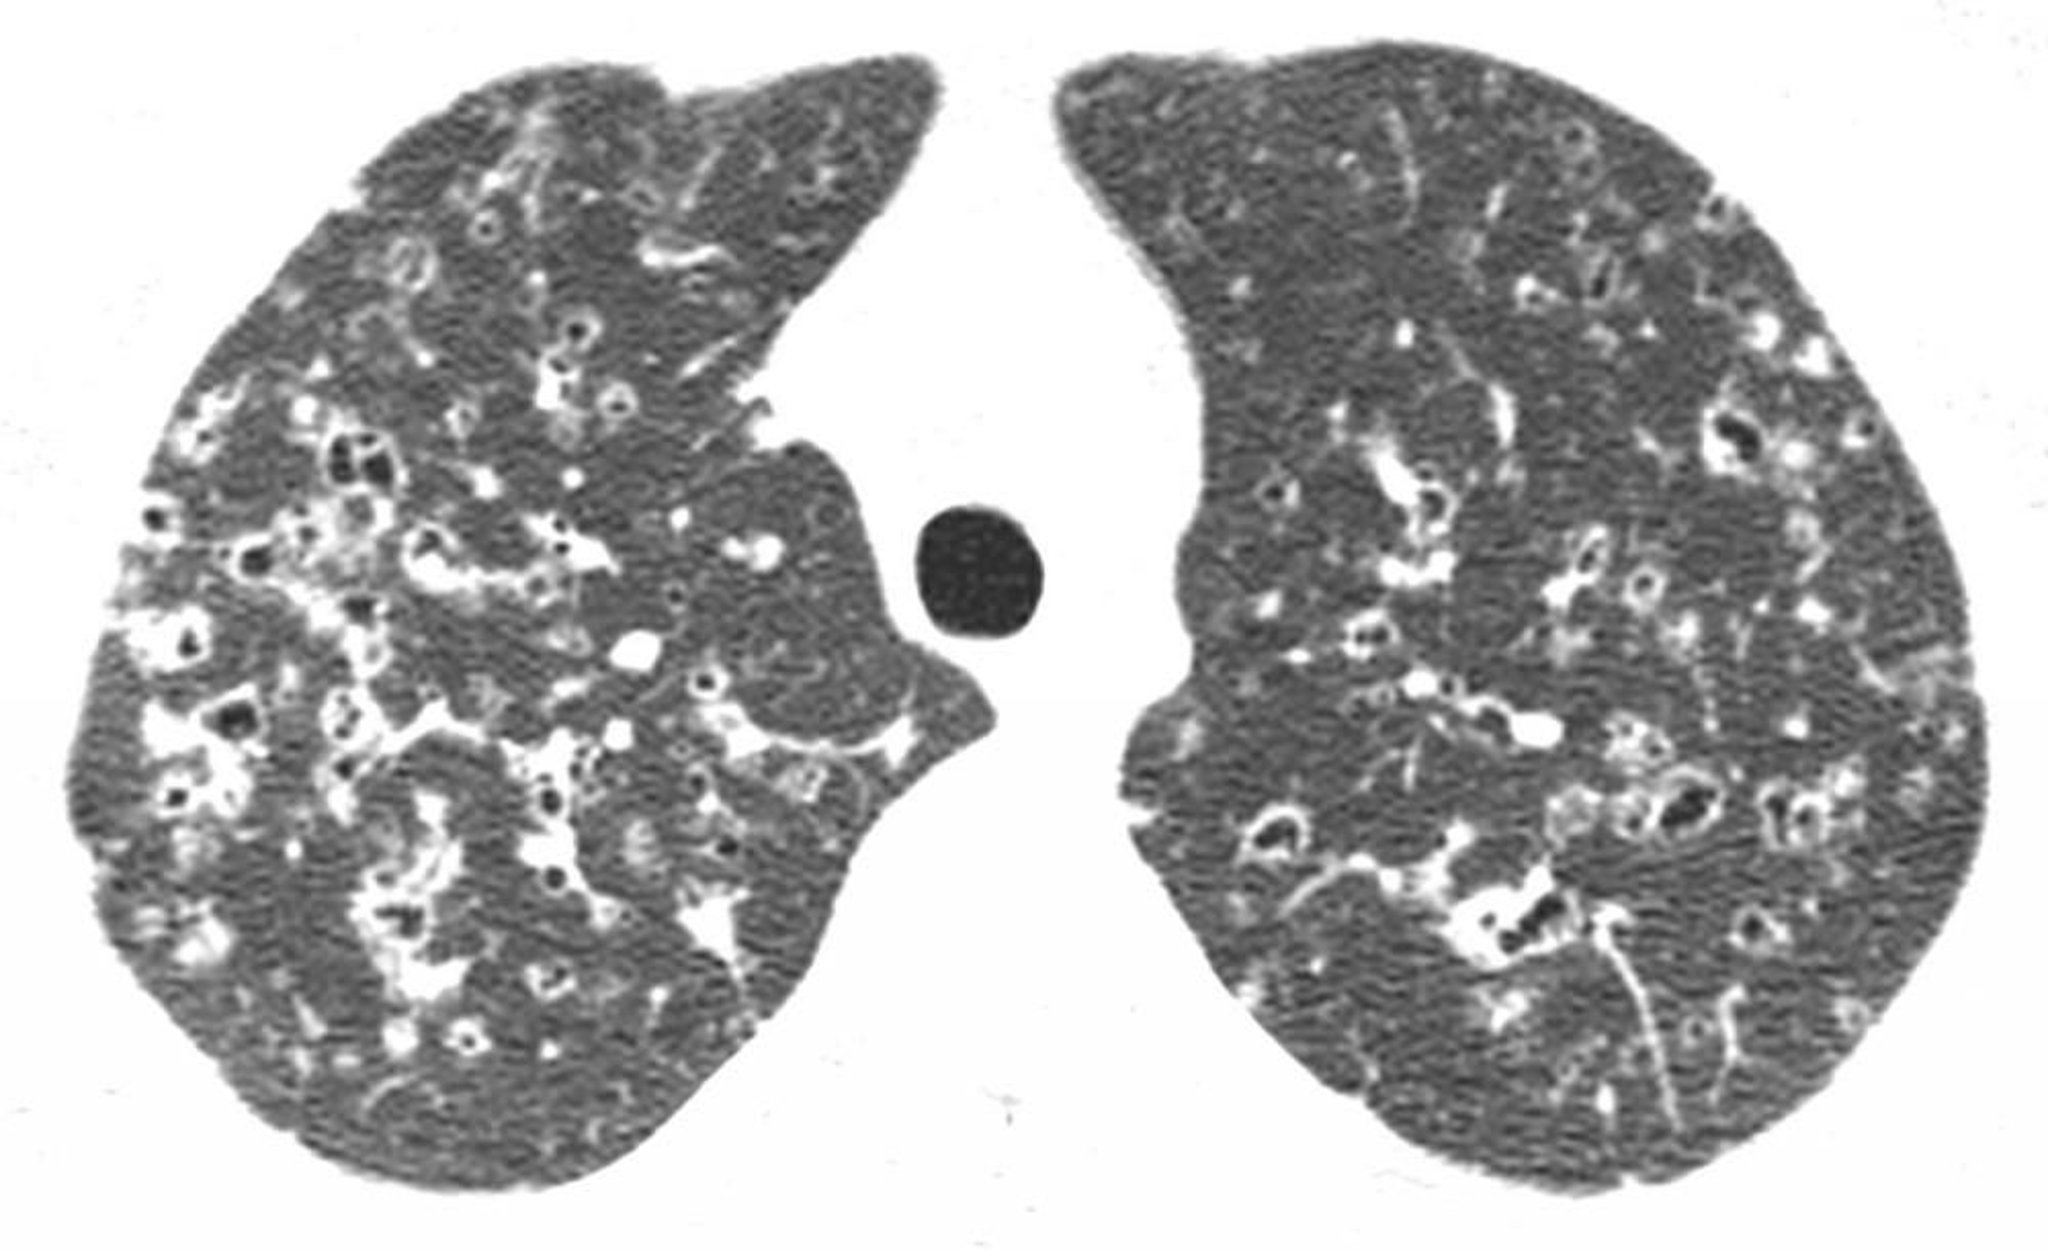

Histiocytose pulmonaire à cellules de Langerhans

La TDM à haute résolution à travers les lobes supérieurs montre des nodules et des kystes de densité aérienne irrégulière, habituellement dans les régions supérieure et moyenne du poumon. Ces signes sont caractéristiques de l'histiocytose à cellules de Langerhans chez un patient qui a des antécédents de tabagisme.

Image courtoisie de Harold R. Collard, MD.